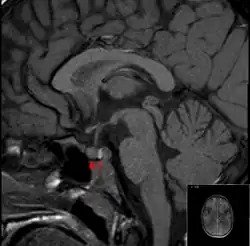

O diagnóstico é feito mediante ressonância magnética sendo o método com maior acuidade, que permite a confirmação do diagnóstico em 90% dos casos. O estudo da tomografia computadorizada do crânio e a análise microbiótica do líquido cefalorraquidiano podem apresentar resultados negativos. O tratamento consiste na correção tempestiva das deficiências hormonais e, em muitos casos, é necessária uma descompressão cirúrgica. Muitos indivíduos que tenham tido apoplexia pituitária desenvolvem deficiência de hormonas hipofisárias, e necessitam de subministração terapêutica para reposição hormonal a longo prazo. O primeiro caso registado da doença data de 1898.[1]

O exame comprobatório gold standard para diagnóstico da apoplexia pituitária é a ressonância magnética, que tem uma sensibilidade superior a 90% para detectar a doença, podendo identificar isquemia (dano tecidual devido à redução do suprimento sanguíneo) ou hemorragia.[1] Podem ser utilizadas várias sequências de ressonância magnética para determinar a ocorrência e a proporção da lesão (hemorragia ou isquemia).[7] Se a ressonância magnética não for indicada (por exemplo, se o paciente se encontra gravemente claustrofóbico ou se tiver implantes que contenham metal), a tomografia computadorizada pode demonstrar anomalias na glândula pituitária, não obstante a falta de fiabilidade.[1]Grande parte dos tumores hipofisários (25%) são detectados graças à individualização, na ressonância, das zonas do enfarte hemorrágico, porém a apoplexia não pode ser diagnosticada se não estiver acompanhada de sintomas.[1][4]